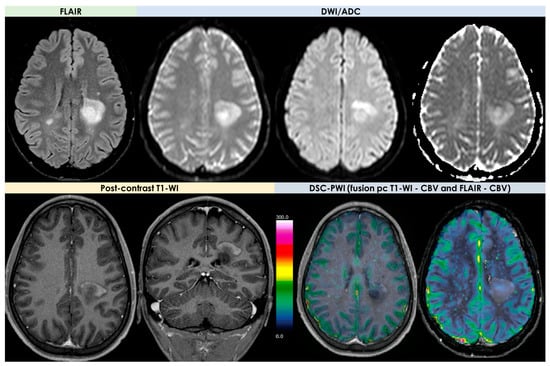

2.4. Advanced MRI Findings

- Dynamic susceptibility contrast (DSC) imaging, which is currently the most commonly used technique;

- Dynamic contrast-enhanced (DCE) imaging (both requiring intravenous administration of a gadolinium-based contrast medium);

- Arterial spin labeling (ASL), not requiring contrast media.

| DWI/ADC | Hyperintense on DWI/hypointense on ADC maps Decreased FA values in lesions | High ADC values in center of lesion and relatively low ADC values in periphery of lesion Threshold for the minimum ADC value for distinguishing TDLs from PCNSL is 0.556 × 10−3 mm2/s | Hypointense in DWI and ADC | Hypointense on DWI and ADC | “Eccentric target sign” consisting of an eccentric nodule along the rim of an enhancing lesion on T1-WI ADC > 1.6 × 10−3 mm2/s suggestive of toxoplasmosis |

| DSC-MRI | rCBV lower than HGG Characteristic TIC | Few data with variable findings | rCBV usually higher than PCNSL, but variable findings | No data | rCBV lower than that in necrotic glioblastomas and metastases |